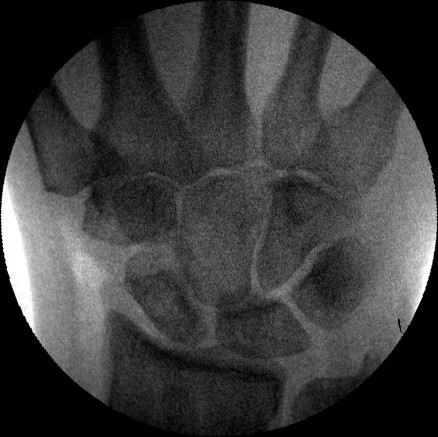

Scapholunate pins and bone anchors - intraoperative fluoroscopy.

Click for larger image